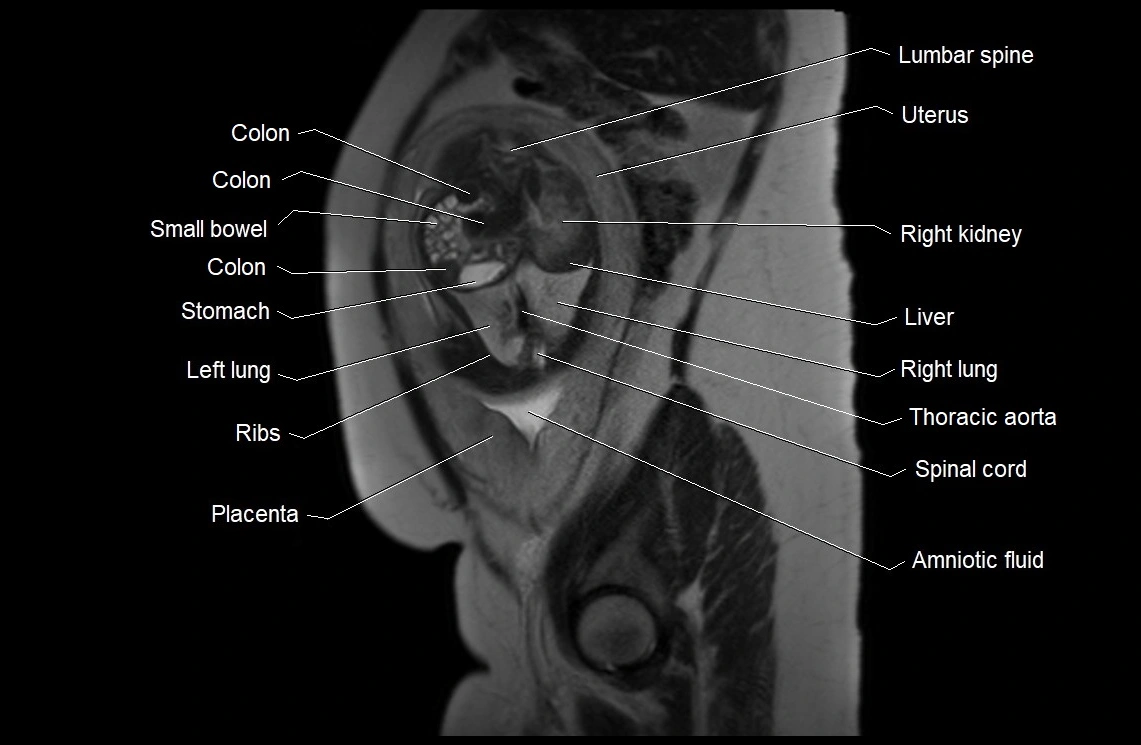

MRI Appearance

T2 HASTE (T2 GRE):

• Amniotic fluid shows very bright hyperintense signal

• Provides natural contrast against fetus and placenta

• Small particles (vernix) may appear as scattered hypointense foci within bright fluid

MRI image

image